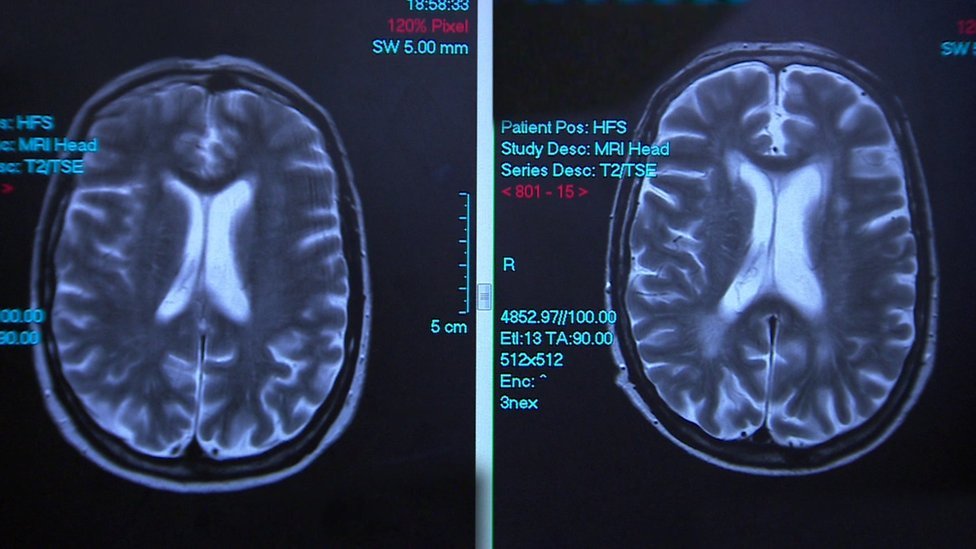

Najosnovniji oblik oštećenja izaziva prekomerna upotreba alkohola, zbog kojeg se mozak smanjuje ili odumire.

Ti ljudi su prvo podvrgnuti testu za dijagnostifikovanje demencije, nakon čega bi usledio skener, kako bi se videlo da li je alkohol doveo od oštećenja mozga.